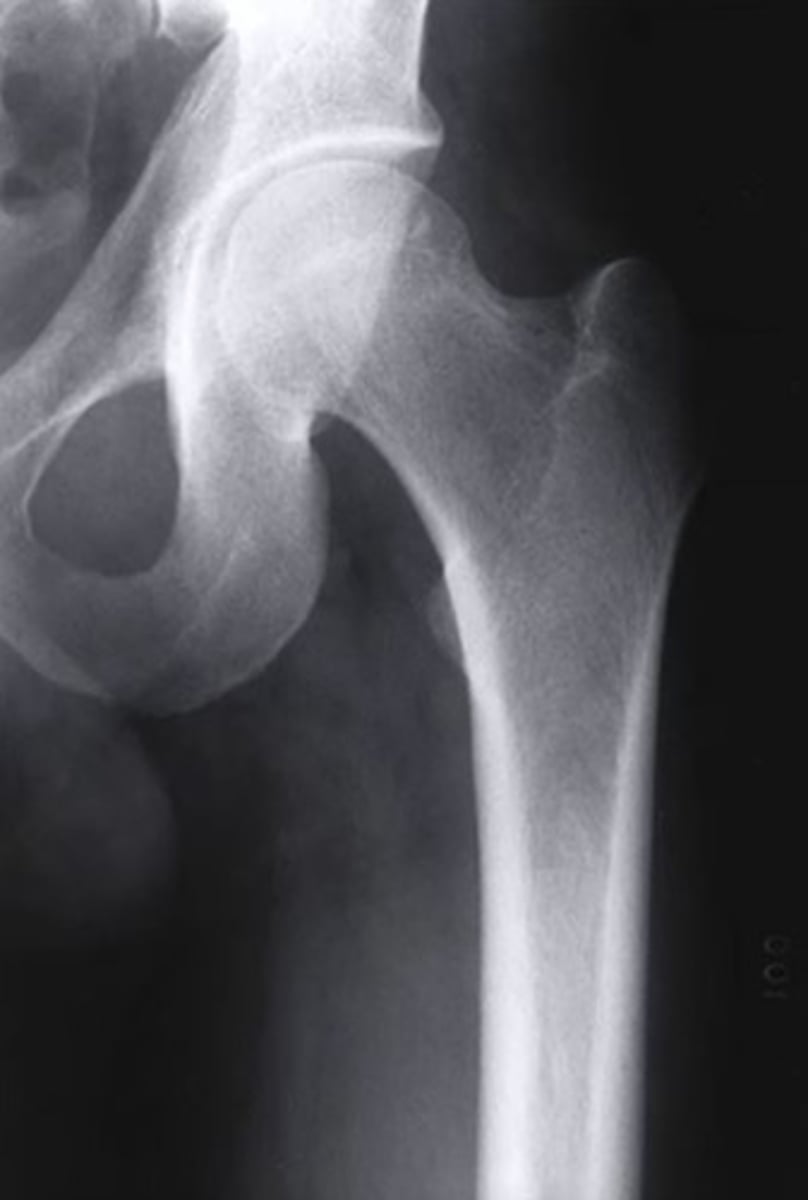

what view is this radiograph?

anteroposterior

3 multiple choice options

what structure is indicated by the orange arrow?

osteochondral fracture of the left femoral head

what are the MRI views of figure 2 and 3, respectively?

coronal and coronal

after revealing an osteochondral fracture of the left femoral head, what should the next steps be for the patient?

discuss with a surgeon for possible surgical options

what is the name of this view of the hip?

AP